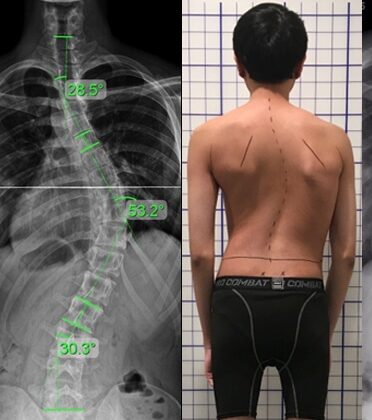

في هذه المقالة سنشرح بطريقة مبسطة نتائج دراسة حديثة قارنت بين شكل العمود الفقري في حالات الانحناء التي تتركز في الجزء العلوي من الظهر (منطقة منتصف الصدر)، وتلك التي تتركز في الجزء السفلي (أسفل الظهر)، مع مقارنة هذه الحالات بالأشخاص الذين لا يعانون من أي انحناء.

شملت الدراسة أكثر من 290 مشاركًا، منهم:

152 مريضًا يعانون من انحناء في الجزء العلوي من الظهر.

50 مريضًا لديهم انحناء في الجزء السفلي من الظهر.

89 شخصًا طبيعيًا لا يعانون من أي انحناء في العمود الفقري.

تم استخدام صور أشعة مزدوجة الاتجاه (من الأمام والجانب) لإنشاء نموذج ثلاثي الأبعاد دقيق للعمود الفقري.

ثم قام الباحثون بتحليل شكل كل جزء من العمود الفقري من أعلى الرقبة حتى نهاية الظهر لمعرفة مقدار الانحناء في كل منطقة.